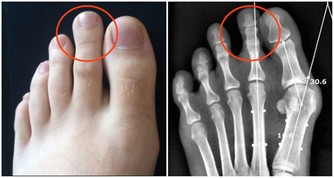

癌症一般是指惡性腫瘤,腫瘤是指機體在各種致瘤因子的作用下,局部細胞組織增生所形成的新組織。它有一個特點,它的生長不受正常機體的生理調節,而是破壞正常的組織和器官。我們所謂的癌症,也就是惡性腫瘤和良性腫瘤相比,具有以下幾個特徵。第一個是生長速度,第二個是容易發生轉移,特別是發生轉移以後,腫瘤的危險性就大大地增加。第三,容易復發。第四,復發最終會導致患者多髒器受損,最終導致患者死亡。

腎臟也一樣,在長期工作壓力和毒素的接觸下,腎臟,尤其是尿液流經的腎小管上皮細胞會發生一些量變,從量變轉變到質變。這時候就產生了腎臟最初的病變。在發生最初病變的時候,隨著病變不斷地長大,這種生長逐漸失去調控,就形成了腫塊,也就是說腎臟上長了一些我們所說的惡性腫瘤。

腎臟的惡性腫瘤分為很多種,最常見的就是腎細胞癌。